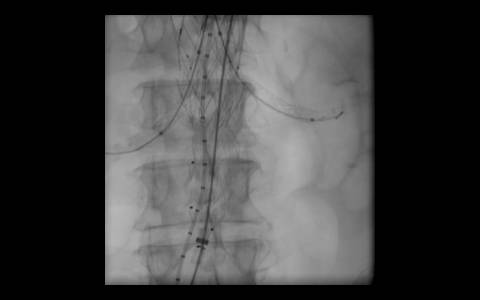

A avaliação por tomografia computadorizada evidenciou um aneurisma infra-renal de colo hostil e acessos vasculares com muita ateromatose. Diante do contexto clínico e de imagem foi optado pelo tratamento endovascular com endoprótese de baixo perfil Incraft CORDIS e técnica de Snorkel Grafts com stents Palmaz CORDIS para as artérias renais.